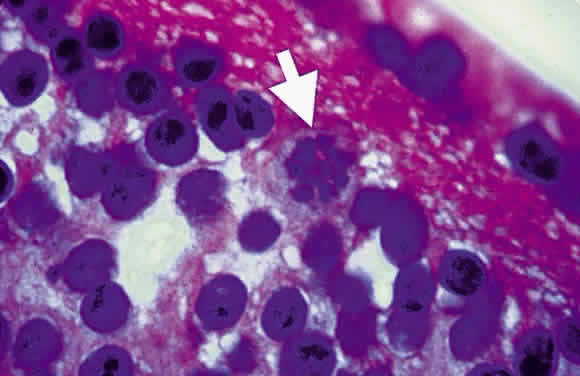

Bradyzoites are slowly metabolizing organisms found in cysts formed within the tissue of the infected host. The size of the Toxoplasma cyst varies, depending on the number of organisms that have multiplied within it. The cyst may reach more than 100 μm in diameter and may contain from 50 to 3000 organisms. The cyst wall is strongly argyrophilic and periodic acid-Schiff positive. It contains constituents that are derived from both the parasite and the host tissue. Constituent from the host tissue compose the outer part of the cyst, whereas those derived from the parasite are in the inner part of the cyst wall. Toxoplasmosis may be found in the inner layers of the retina after episodes of acute retinochoroiditis. The cyst may stay in the retinal tissue for years without showing any signs of invasiveness. Considering that the tissue cyst incorporates elements derived from the host into its outer wall, it is easily tolerated by the host, and no inflammatory reaction is seen around it (Fig. 2). It may remain for years in certain tissues, such as the eye or muscles, without provoking any inflammatory reactions. The bradyzoite inside the cyst derives its nutrition from the slow diffusion of substances through the cyst wall. The number of organisms increases within the cyst in the retina, and once the cyst wall breaks down by mechanical stretching, the bradyzoites escape, convert into tachyzoites, and invade contiguous cells. This process may lead to recurrence of retinitis. Certain immunologic mechanisms of the host may influence the organisms significantly. Immunosuppression coinciding with the rupture of the cyst and release of bradyzoites allows the organisms to become tachyzoites and proliferate in host tissue without restriction. The cyst of the Toxoplasma organism appears to be a defensive stage in its life cycle. The resistance of toxoplasmosis within chronically infected tissues of animals may lead to transmission of the disease by the ingestion of undercooked meat, including mutton, beef, pork, and chicken. Tissue cysts can develop within any organ and are commonly found in infected tissues of brain, eye, heart, skeletal muscles, and lymph nodes. Rupture of tissue cysts causes reactivation of the systemic toxoplasmosis in immune deficiency states, leading to dissemination of Toxoplasma organisms to other organs.